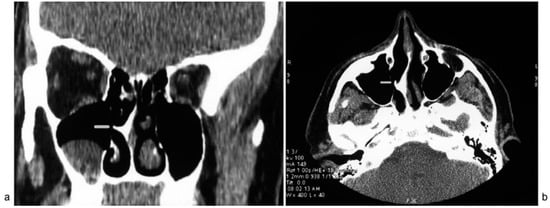

A 19-year-old man was presented with a 5-year history of right-sided otalgia and tinnitus. The pain was deep and penetrating in character, intermittent, and lasted for 4 to 5 h, radiating to the right mastoid region. Tinnitus was in the form of whistle and also intermittent with the same duration as otalgia. The patient reported the right-sided nasal obstruction only during the attacks of otalgia and tinnitus. He had no history of head trauma and surgery and he was treated for migraine and otitis media without success. The otoendoscopic examination revealed normal right-sided external auditory canal and tympanic membrane (Figure 1) and the audiological evaluation showed a normal hearing. During rhinoscopic and nasal endoscopic examination, there was no sign of inflammation. The author found a normal nasal mucosa with a mucosal contact between the large, right-sided septal spur and lateral nasal wall, which was confirmed by computed tomographic (CT) scan of the paranasal sinuses (Figure 2a,b). During an otalgia attack, the author placed a small 5% lidocaine and epinephrine-soaked cotton pledget on the contact point and, after 15 min, the patient experienced a significant reduction in intensity of earache and tinnitus. The patient underwent a septoplasty under general anesthesia. A few days postoperatively, the patient was free of otalgia, with significant improvement in tinnitus intensity, and without the right-sided nasal discharge. At 12 months follow-up, the patient reported no further otalgia and tinnitus.

Figure 2.

Coronal (a) and axial (b) CT scan of the paranasal sinuses showing mucosal contact (arrows) between the peak of septal spur and the surface of the right lateral nasal wall and a retention cyst inside the right maxillary sinus.